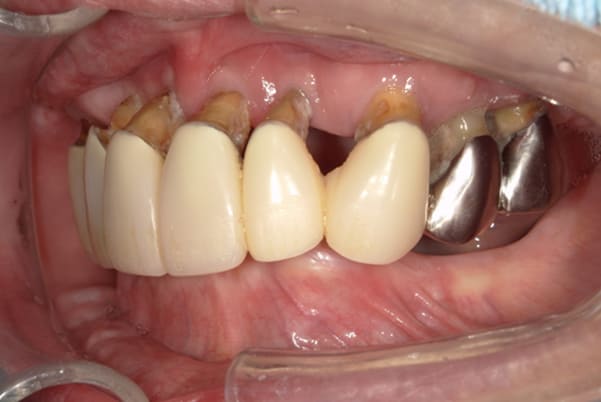

症例レポート[CASE.04]

前歯がとれて痛い、

食事もできず、見た目も悪い

- 性別・年齢

- 女性(60代)

- 主訴

- 前歯がとれて、痛い、食事ができない、見た目が悪く人に会えないので何とかしてほしい

- 治療

-

- 上顎精密金属総入れ歯

- 下顎精密金属部分入れ歯

- 磁性アタッチメント(白金加金) 1歯

- 治療期間

- 約5か月間

- 費用

- 上顎精密金属床総入れ歯:55万円

- 下顎精密金属床部分入れ歯:55万円

- 磁性アタッチメント:11万円×1歯

(白金加金)

合計:121万円(税込)

上前歯はブリッジの差し歯により根が折れ炎症を起こしお痛みのある状態でした。

原因は長期使用により下の義歯の歯が削れたことにより、下前歯が上前歯を突き上げ強い力が加わっていたことが根本的な原因と考えられます。

治療前は、奥歯が下がり、かみ合わせが乱れています。適切な入れ歯はそのままのかみ合わせで義歯を作るのではなく治療後のように、前歯から奥歯までのラインが真っすぐ揃った、かみ合わせの面を適切に付与し、よく咬め、残りの歯に負担がかからないかみ合わせとしました。

とにかく何も食べられないこと、人に会えないことから、なるべく早く何とかしたいとのご希望でした。

患者様とご相談の上、まず早急に上記を回復させるため、初診含め3度の来院でお食事ができ、見た目を回復できるように治療用義歯を作製、装着しました。

本来は、数本の上前歯の折れてしまって残せない歯は抜いてから歯肉の治癒を待ち、数か月後に型どりから作製になりますが、抜歯即時義歯といって、歯を抜く前に型、かみ合わせをとり、抜歯を行ったその日に上下の義歯を装着する特殊な治療法を用いたことで、10日後には治療用義歯をお口に装着することができ、お痛みもなくお食事ができ、ご友人とのお食事にも行けることが可能になりました。

本来、入れ歯作製は技工所と言って、義歯を作製する所に発送するため、作製には時間がかかりますが、院内に技工専用スペースを完備しており、長年、義歯治療において、技工も技術の習得してきましたので技工士さんではなく、かみ合わせの道具も私自身で院内で作製したことで、初診日の次の日にご来院いただきかみ合わせを採ることで、診断、型どり、かみ合わせ、装着まで10日という最短のご希望にこたえらた方です。

ここから、最終的な義歯の作製は従来通り行いました。

抜歯した歯肉が治癒するのを待っている間に、細かなかみ合わせ調整や、審美的なご希望、違和感などをお伺いしそれをもとに、最終義歯を作製しましたが、その作製中も治療用義歯は快適にお使いいただけるため、普段の生活を行いながら通院していただくことが可能となりました。

お写真は治療用の仮の入れですが普段通りお食事ができるとのことで少し食べ物もついています。。。

上顎治療前

上顎治療後

根のみの7本は虫歯にもなっており歯肉は腫れあがっています。

残りの歯もレントゲンで重度の歯周炎によりぐらぐらな状態でした。

下顎治療前

下顎治療後

治療前の入れ歯の奥歯は、治療後の義歯と比較しても分かるように、歯が削れ平らになった状態です。

これにより奥歯のかみ合わせは低くなり、前歯のみが強くあたり、かみ合わせにより上の前歯大きな負担がかかっていたことにより、上の前歯が折れたことが考えられます。